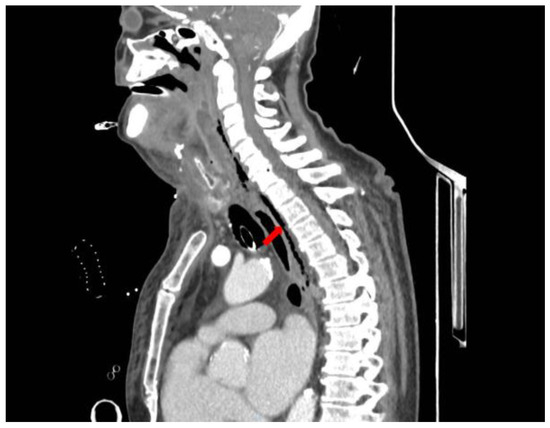

Introduction: Eggerthia catenaformis, a non-spore-forming anaerobic Gram-positive bacillus component of the human fecal microbiota has rarely been reported in human diseases. In almost every case described in current literature to date, dental diseases (abscesses, periodontitis, or caries), are the most common source of the infection which extends to the brain, cervical spaces, pulmonary parenchyma, the pleural cavity, the abdominal wall, and the abdominal cavity. Case report: An 82-year-old male Caucasian patient was admitted to our Emergency Department (ED) with a painless, right submandibular mass, dyspnea, and inspiratory stridor. A CT scan of the head, neck, and chest with intravenous contrast material revealed a retrotonsillar fluid collection. Air bubbles and minimal fluid were present from the right sub-mandibular area to the lower mediastinum between the spine, the descending thoracic aorta, and the trachea. The patient underwent surgical treatment and a broad-spectrum antibiotic. The retropharyngeal fluid collection culture showed the presence of Eggerthia catenaformis. After a first period in the Intensive Care Unit, he was admitted to a Step-Down Unit (SDU) where he underwent respiratory weaning, motor rehabilitation, and gradual oral feeding resumption. At discharge, the patient maintained the tracheal cannula as he still had impaired swallowing of solid foods. Conclusions: Here we report the first case of descending necrotizing mediastinitis in a patient with a retropharyngeal abscess, in the absence of dental diseases. Full article

Show Figures

Figure 1